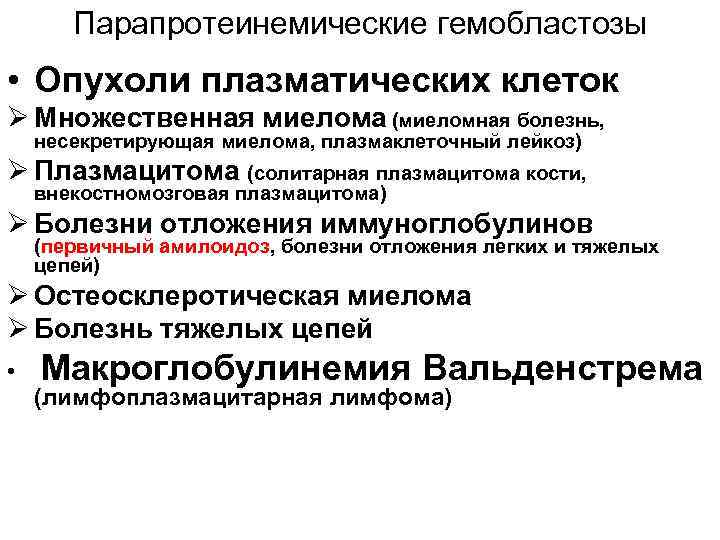

Парапротеинемические гемобластозы • Опухоли плазматических клеток Ø Множественная миелома (миеломная болезнь, несекретирующая миелома, плазмаклеточный лейкоз) Ø Плазмацитома (солитарная плазмацитома кости, внекостномозговая плазмацитома) Ø Болезни отложения иммуноглобулинов (первичный амилоидоз, болезни отложения легких и тяжелых цепей) Ø Остеосклеротическая миелома Ø Болезнь тяжелых цепей • Макроглобулинемия Вальденстрема (лимфоплазмацитарная лимфома)

Парапротеинемические гемобластозы • Опухоли плазматических клеток Ø Множественная миелома (миеломная болезнь, несекретирующая миелома, плазмаклеточный лейкоз) Ø Плазмацитома (солитарная плазмацитома кости, внекостномозговая плазмацитома) Ø Болезни отложения иммуноглобулинов (первичный амилоидоз, болезни отложения легких и тяжелых цепей) Ø Остеосклеротическая миелома Ø Болезнь тяжелых цепей • Макроглобулинемия Вальденстрема (лимфоплазмацитарная лимфома)